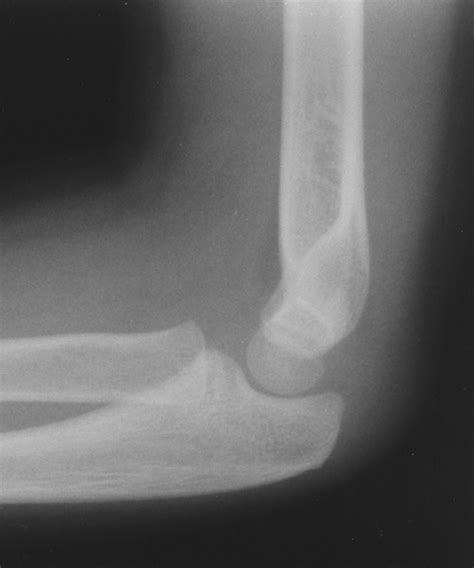

The diagnosis of moderate joint effusion typically involves a combination of physical examination, imaging studies, and laboratory tests. Physical examination may reveal joint swelling, warmth, and limited mobility, while imaging studies such as X-rays, ultrasound, or magnetic resonance imaging (MRI) can help confirm the presence of excess fluid within the joint space. Laboratory tests, including complete blood count, erythrocyte sedimentation rate, and C-reactive protein, can help identify underlying inflammatory or infectious conditions.